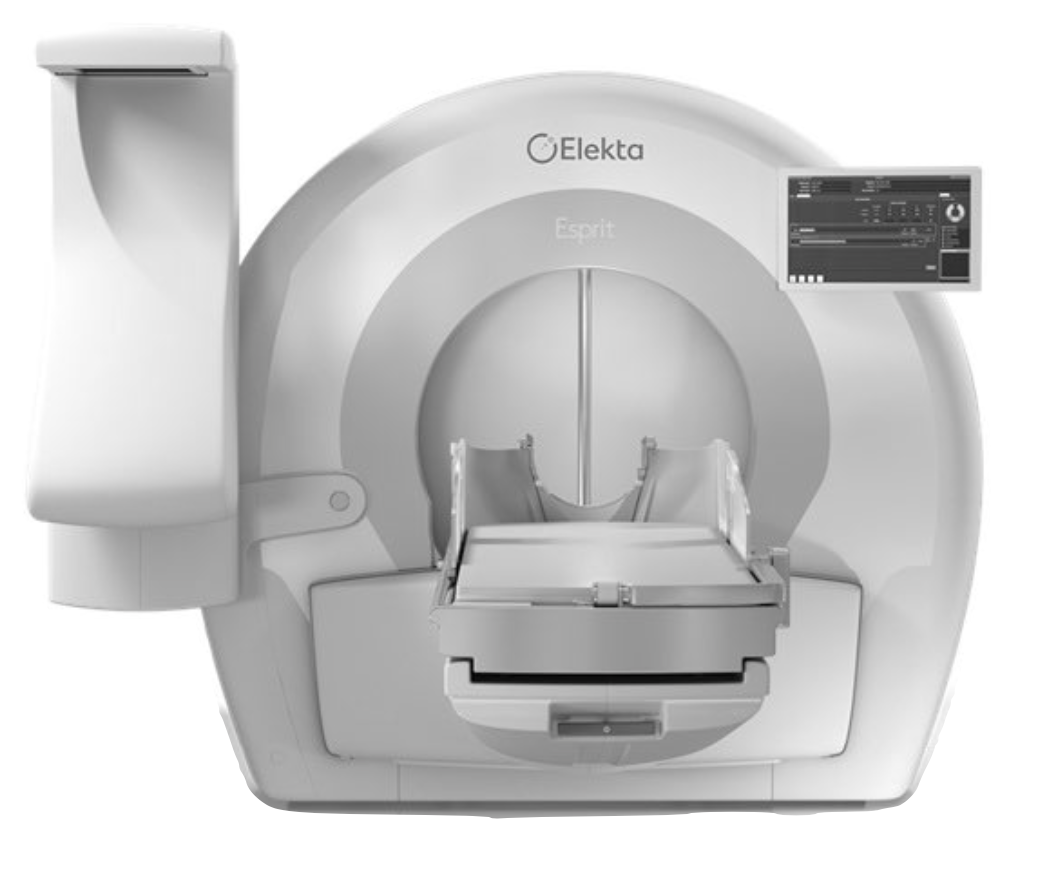

Advanced otology encompasses complex ear and skull base conditions requiring specialized surgical care. We offer cochlear implants and bone conduction implants for hearing loss, treat acoustic neuroma and temporal bone tumors, and perform stapes surgery for otosclerosis. Our team also manages cholesteatoma, superior canal dehiscence, and other advanced ear conditions. Select a topic below to learn more.